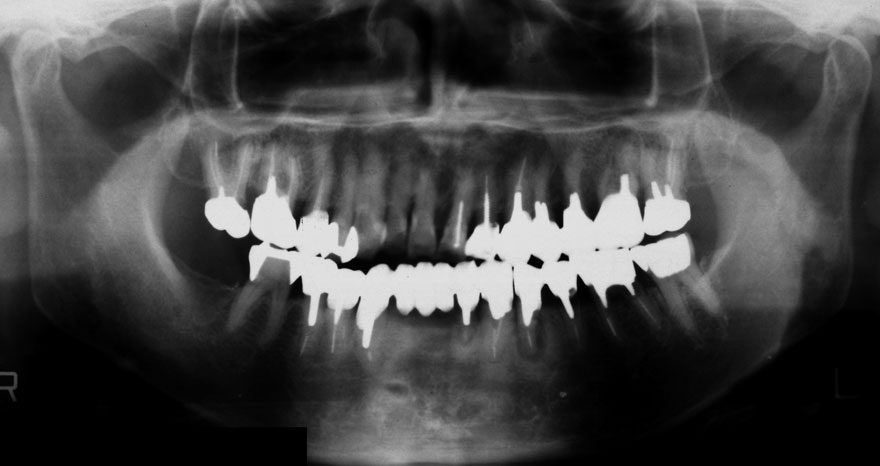

初診時 60歳 男性

29年後 89歳